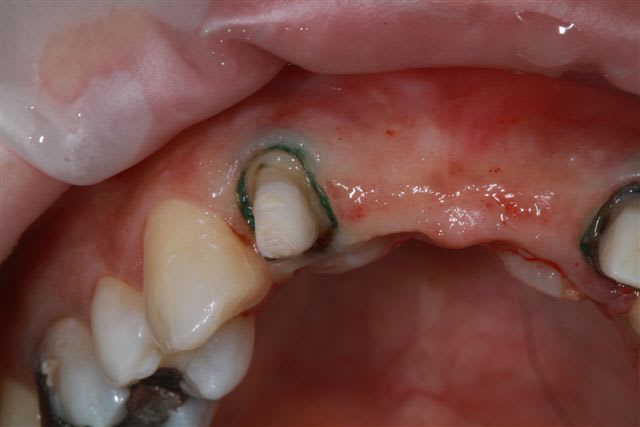

sur-traitement, pompe à fric, assassinat ...etc.. afin d'éviter tout ça je soumet à votre sagesse un cas sympa.

Patiente sympa, 30 ans, un bridge ceramo-métal fait il y a 10 ans, en fin de vie.

la suite

reconstitution, taille pour empreinte et provisoire (pas beau mais il sera remplacé)